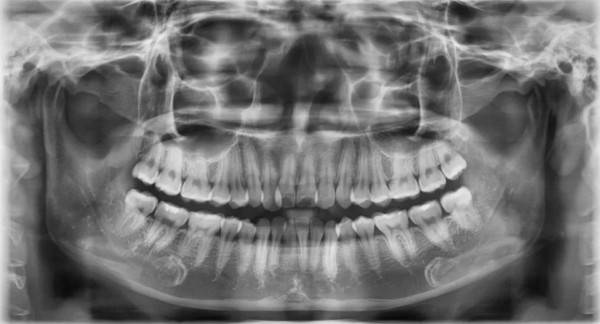

Chụp phim Panorama toàn cảnh

Chụp phim toàn cảnh (phim Panoramic) được sử dụng để quét toàn bộ cấu trúc răng, hàm và các cấu trúc lân cận như xoang, hàm mặt. Loại hình này thường được chỉ định trong các ca phẫu thuật, trồng răng, phát hiện các vấn đề về xương hoặc các bất thường bên trong khung hàm.

Chỉ với khoản chi phí khoảng 300.000 – 700.000 đồng, bạn đã có thể sở hữu một hình ảnh toàn diện, giúp bác sĩ có hướng xử lý phù hợp nhất. Công nghệ hiện đại của máy phim toàn cảnh giúp giảm thiểu phóng đại, hạn chế nhiễu và nâng cao độ chính xác của kết quả. Đây là lựa chọn tối ưu để có cái nhìn tổng thể, đặc biệt phù hợp cho các ca điều trị phức tạp.